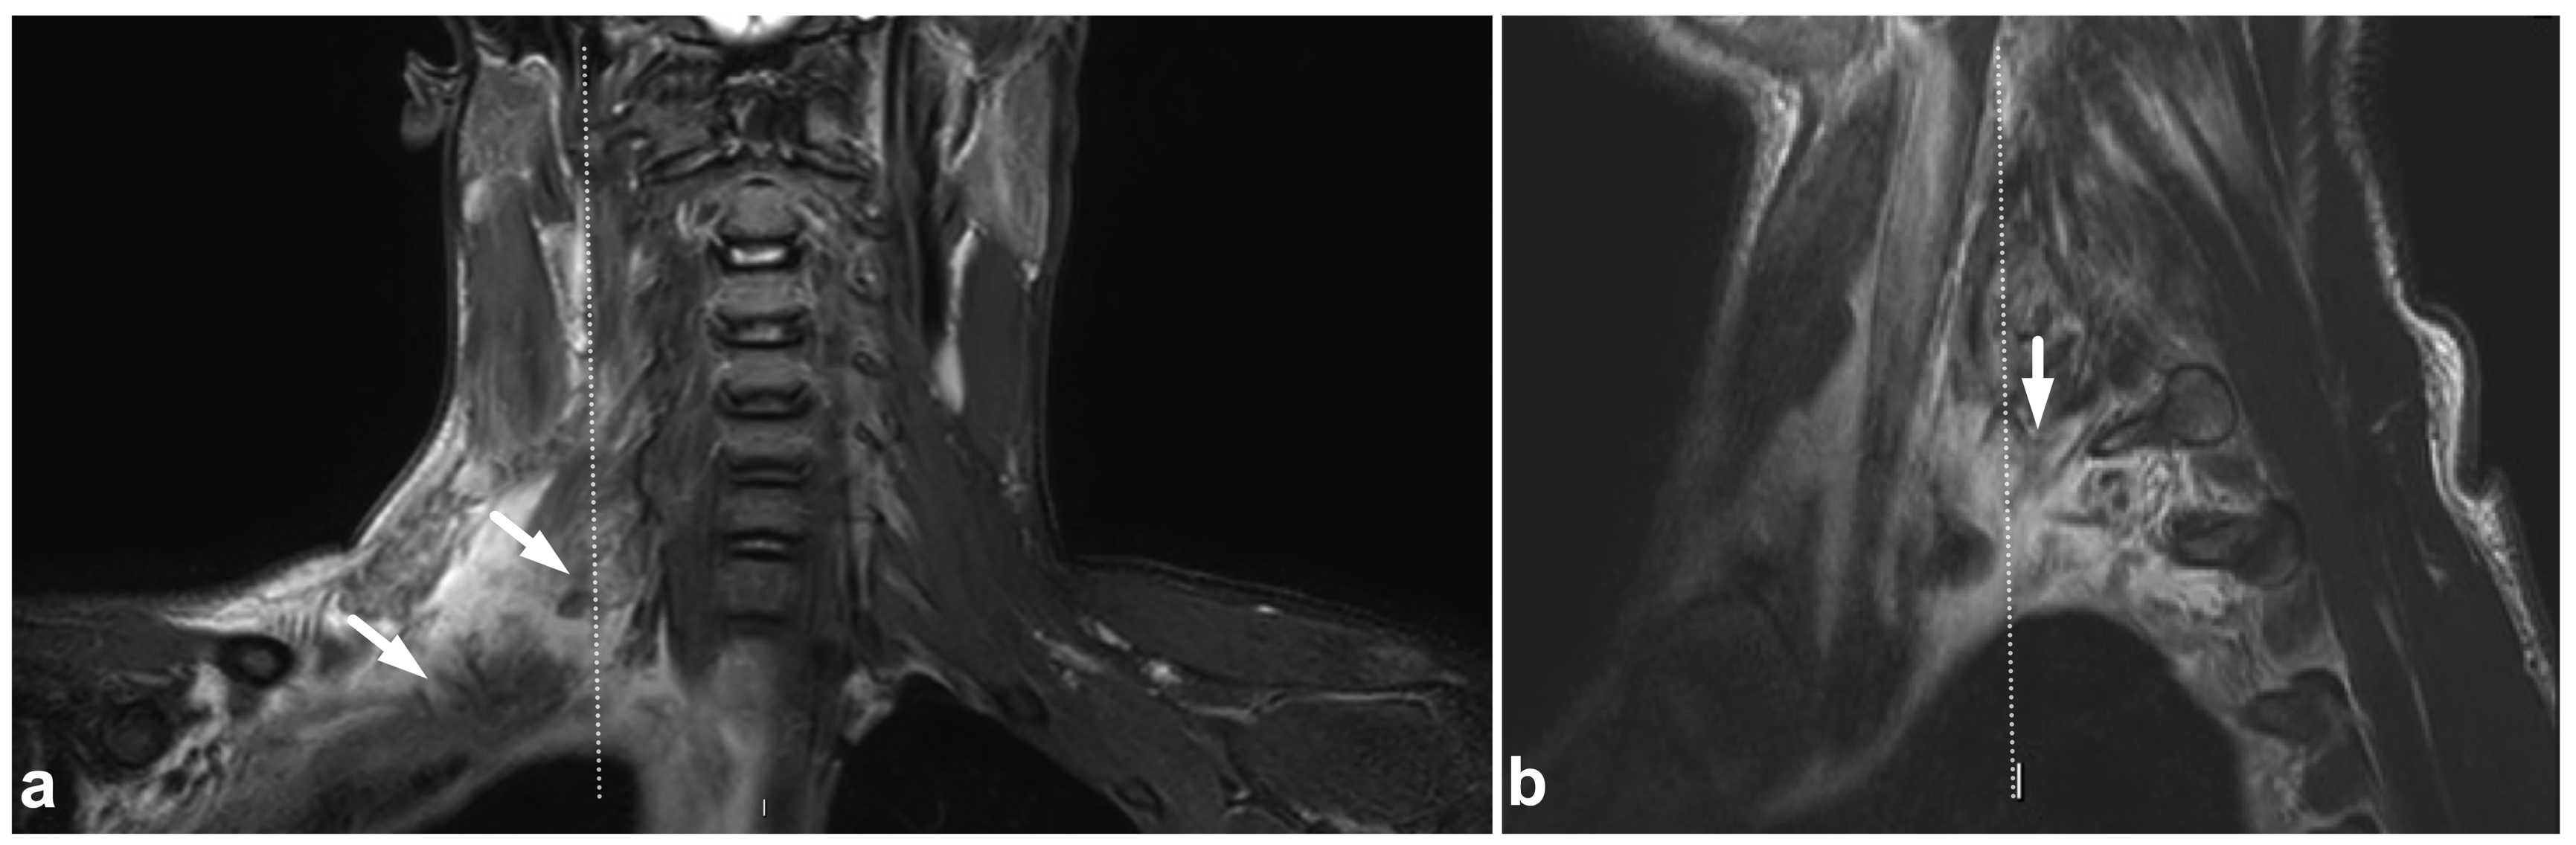

5.3. Nerve Plexus Injuries